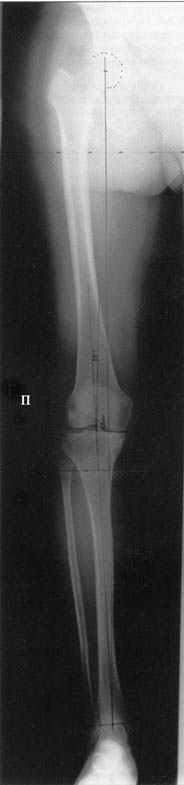

Большая просьба прокомментировать прилагавшиеся снимки. Видно, что сделано что-то красивое, но не совсем понятно, по какому поводу, как рассчитывалась коррекция, и что именно сделано.

Поводом для проведения всех корригирующих остеотомий у исследуемых пациентов служил гонартроз 1-3 стадии, косметическая коррекция в большинстве случаев являлась вторичной.

Хотя любого больного она не в меньшей степени интересовала. При всех видах остеотомий обязательным требованием являлась восстановление баланса пассивных и динамических сил путем восстановления оси конечности, стабильности связочного аппарата и контроля над мышечной активностью при осевой нагрузке. Как правило, учитывалась сохранность гиалинового хряща на компенсирующем нагрузку мыщелке бедра или большеберцовой кости. Предоперационное планирование осуществляли с поднагрузочных рентгенограмм обоих конечностей.

Поделитесь, пожалуйста, опытом, как Вам удается выполнять такие качественные рентгеновские снимки всей ноги полностью? На трех кассетах одновременно? Стыки кассет обычно <крадут> 1-2 см изображения. На снимке Вашего пациента <украденных> участков нет!

Качественные под нагрузочные рентгеновские снимки, получаются благодаря современному рентгеновскому оборудованию фирмы SIEMENS, (подробности могу уточнить у рентгенологов), а качественно стыковать (прозрачный скотч) научились с годами, но это для публикаций, для работы достаточно скрепить степлером по анатомическим осям с учетом толщины диафизов и грамотно расчертить. Пособие с удовольствием отправлю.